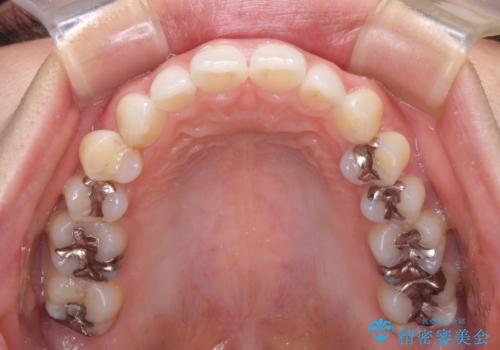

- 口元の突出感と口の閉じにくさを気にして来院された患者様です。

上下左右第一小臼歯4本を抜歯し、ワイヤー装置にて口元を引っ込めるよう矯正治療を行うこととしました。

奥歯が前方に傾斜していることで深く咬みこむ(ディープバイト)状態であったので、なかなか抜歯したスペースが閉じず、様々な方法でディープバイトを改善しながら治療を進めていくこととなりました。